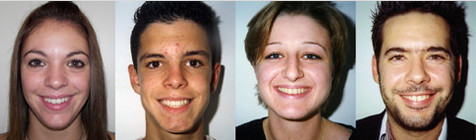

Φυσιολογικό στόμα είναι εκείνο που

- οι γνάθοι (οστά) έχουν την σωστή ανάπτυξη και ορθές σχέσεις μεταξύ τους ως προς τις τρεις διαστάσεις του χώρου

- τα δόντια βρίσκονται σε καλές θέσεις μεταξύ τους και σχηματίζουν δύο ωραία τόξα όπου το επάνω τόξο είναι λίγο πιο ευρύ από το κάτω

- η μέση γραμμή των επάνω δοντιών συμπίπτει με την μέση γραμμή των κάτω δοντιών